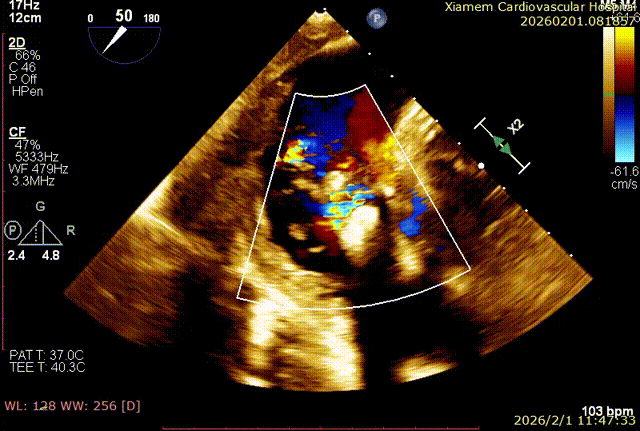

T-TEER 手术过程术前 TTE+TEE 评估:全心扩大,右房横径 8.3cm,左房横径 5.2cm;三尖瓣房性功能性反流,Type ⅢB 型(后叶为两瓣),反流程度 4+(Massive),缩流颈宽度 VC 为 14.5mm;TAPSE 为 1.3cm, LVEF(%)为 72%。

第一个夹子释放后,在前叶、隔叶间靠近中央区仍有残余反流,所以决定再植入一枚 6mm 夹合器。第二枚夹合器抓捕瓣叶过程中,受到第一枚夹合器影响,无法清晰的在 X-plane 切面上进行瓣叶捕获,因此改用 3D-MultiView 切面顺利抓捕,关闭夹合器后残余反流已经由术前极重度(4+)减小为轻中度(2+),手术过程流畅,手术结果完美。

术后即刻反流改善为2+